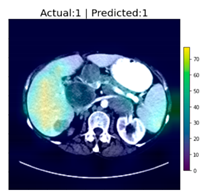

As an interesting sidenote: During the testing phase of the CNN classifier, an investigator noted that it appears that tumors in certain body regions appeared to have a higher rate of classification accuracy than images of other regions. Although it was not in the original plan, an impromptu experiment was conducted to test this hypothesis. From the 1700 original samples, those that contain tumors in specific regions of the body, i.e., the liver and lungs, were grouped together. The reason we chose these two regions is that patients residing in the Asia-Pacific region are more susceptible to cancers in these regions [20], and symptoms of cancers in these regions also tend to be ignored by patients in their early stages because these symptoms can be insignificant. If these types of cancer can be detected at an early stage, then treatments with higher rates of success can be prescribed.

The two groups, liver cancer, and lung cancer were trained and tested separately. The final results appear to justify the earlier suspicions: the classification of tumors in the lung region achieved 98.126% accuracy, while the classification of those in the liver region achieved an astounding 100% accuracy. However, because their sample sizes are small, the results are not truly representative. It is, however, an interesting observation even though the results are not useful for the Grad-CAM experiment due to the small sample sizes. The following figures, Figure 7 and Figure 8, show the sample outputs of these experiments, where “Yes/No” indicates whether a tumor was detected, and the values of “1/0” are DeepLesion labels, where “1” indicates the image contains tumor”, and “0” indicates “has no tumor”.

Figure 7.

Examples of classification of CT images containing lung tumors.